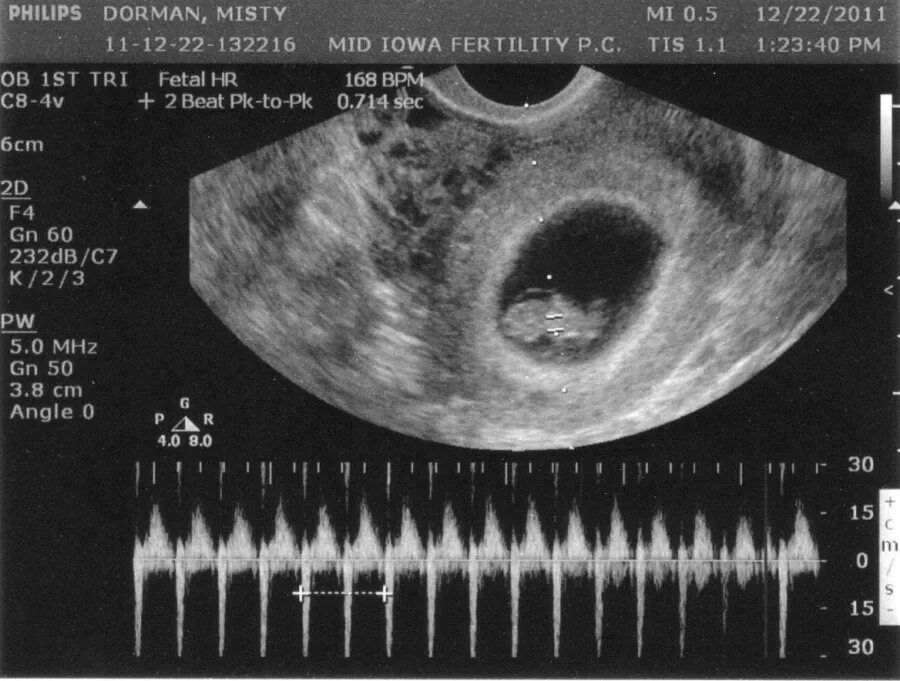

1 9 неделя беременности